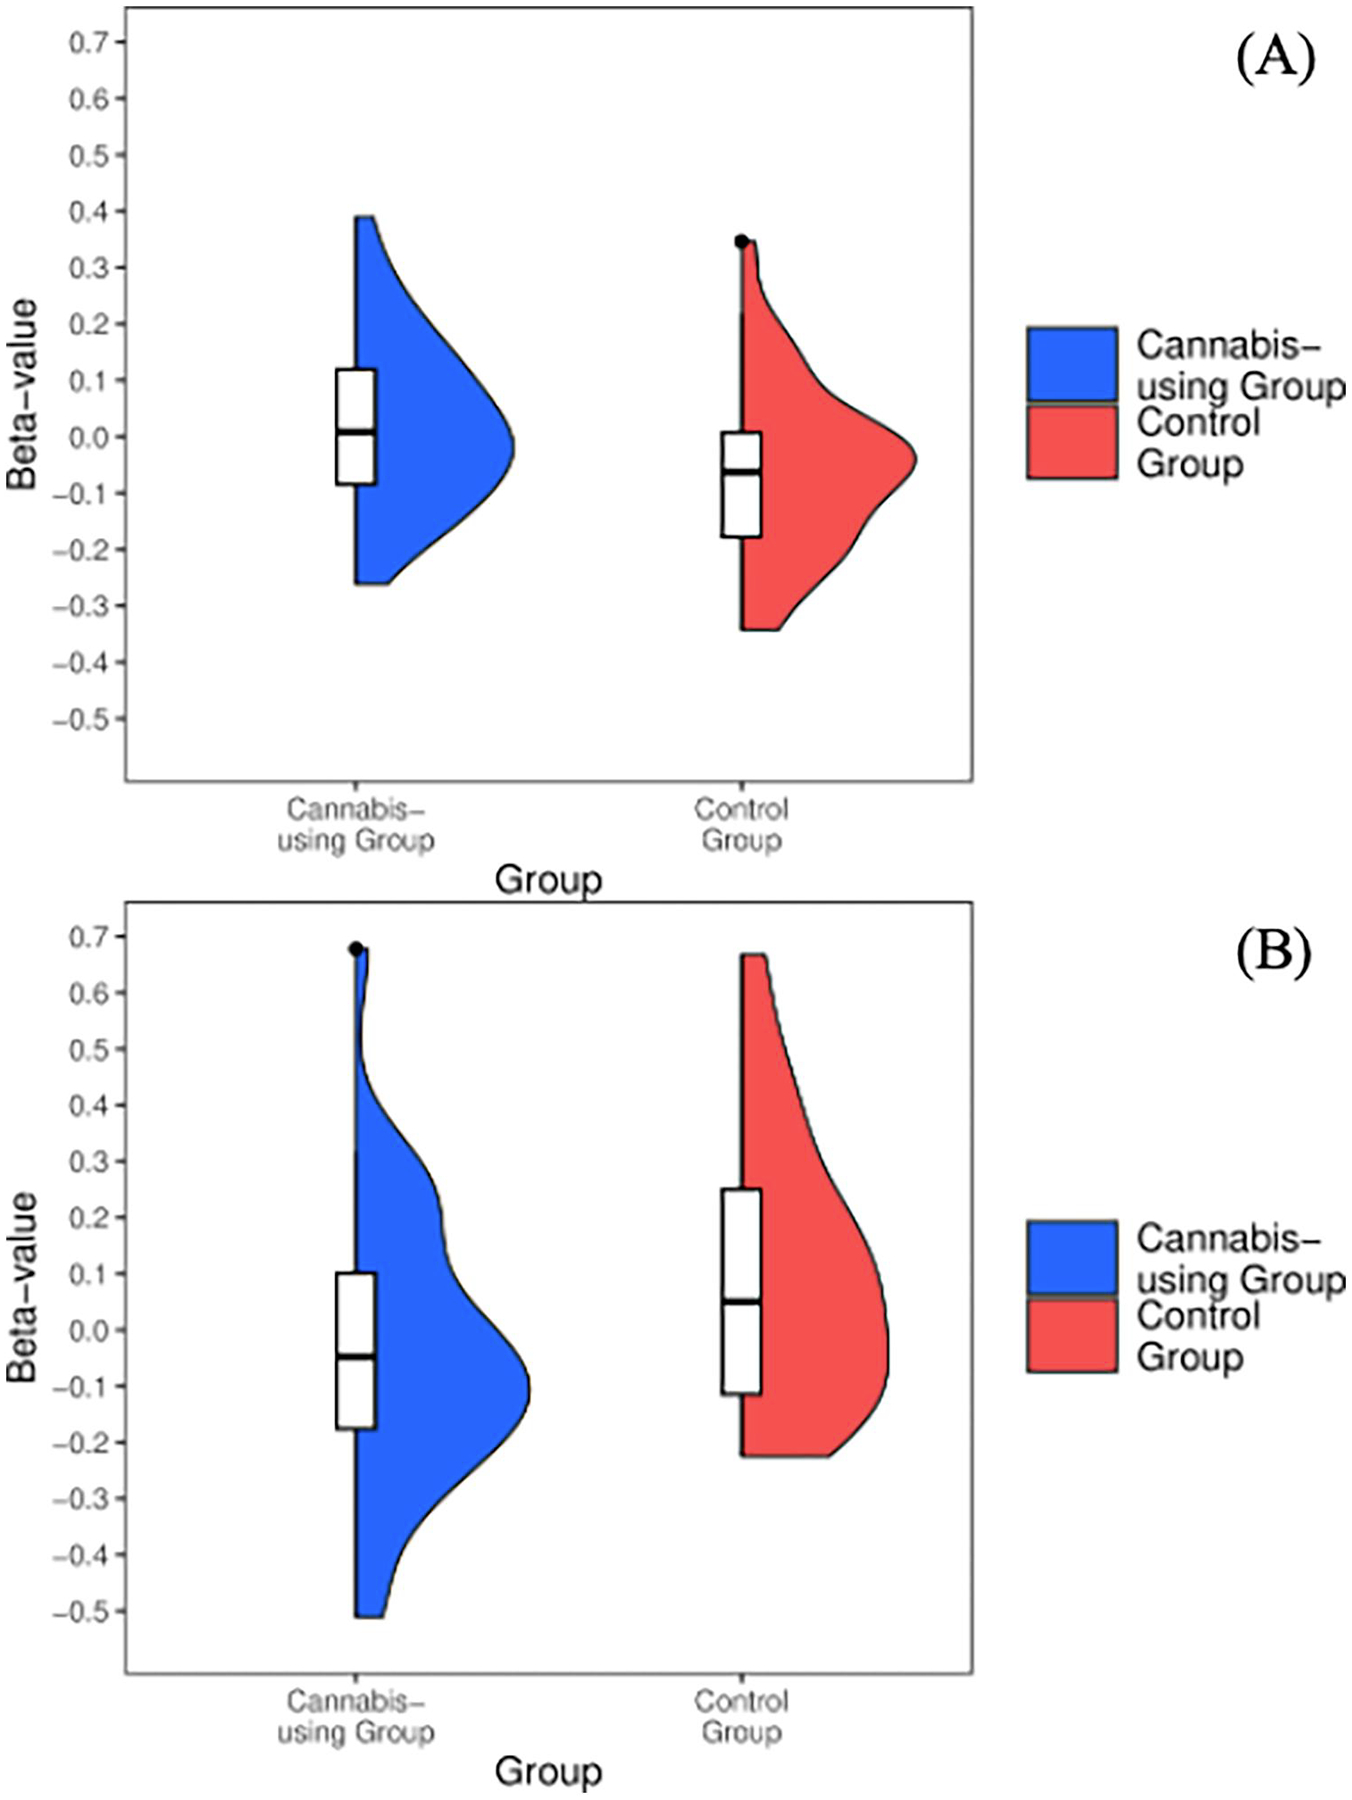

Bilateral ventral striatal seed activation

Overall positive > neutral faces

Cannabis-using participants did not differ from controls in ventral striatal activity during all positive face conditions (p = .25).

Positive > neutral go

Cannabis-using participants demonstrated increased (M = 0.02, SD = 0.15) activation in the ventral striatum during positive Go conditions [t(64)=−2.24, p = 0.02] when compared to controls (M = −0.06,SD = 0.15) (see Figure 3A).

Positive > neutral No-Go

Cannabis-using participants demonstrated decreased activation (M = −0.04, SD = 0.24) in bilateral ventral striatum during positive No-go conditions [t(64) = 2.62, p = 0.01] when compared to controls (M = 0.1, SD = 0.24) (see Figure 3B). No effects of covariates were observed.

Bilateral ventral striatal seed connectivity (gPPI)

Across all conditions (i.e., overall positive > neutral faces, positive > neutral Go, and positive > neutral No-go) no clusters of connectivity with the bilateral ventral striatum seed survived thresholding.

Analyses additionally observed increased ventral striatum activity during positive response conditions, which corresponds with hyperactivation seen during the reward outcome trials on the MID task among cannabis-using groups (ref. 30, ref. 45, ref. 46). This may possibly represent shared activation patterns for positive facial stimuli and monetary reward stimuli. Hyperactive regions observed within our cannabis group may be indicative of increased recruitment in order to complete the task similar to their non-using peers (i.e., maintain rule set to initiate motor response to positive faces); alternatively, increased activation in cingulum and ventral striatum regions could demonstrate sensitized responses to reward processing within cannabis-using groups, despite similar behavioral performance and abstinence length. Lastly, decreased left supplemental motor activation observed is consistent with findings specifically on tasks requiring motor response (ref. 92, ref. 93). As all three regions (left middle cingulum, left supplemental motor, and ventral striatum) are rich in CB1 receptors (ref. 94, ref. 95), aberrant activation in these areas may be suggestive of compensatory mechanisms by which cannabis-using participants are more heavily recruiting middle cingulum and ventral striatal regions due to positive nature of task condition, while non-using controls more readily engage supplementary motor areas to respond to positive stimuli.

Decreased left superior frontal and ventral striatum activations were observed in positive response inhibition (i.e., happy No-go) for cannabis-using participants relative to controls. Studies of BOLD activation elicited by inhibitory tasks have shown that cannabis-using groups generally display aberrant BOLD response in frontal regions (ref. 59, ref. 61, ref. 84, ref. 96). In a similar sample, Wallace et al. (ref. 13) found increased activation in left frontal gyrus when examining response inhibition to calm (i.e., neutral) faces. Further, given the mixed findings on BOLD response elicited by positive stimuli (ref. 52, ref. 56, ref. 57), we demonstrate a unique pattern of left superior frontal activation in inhibitory trials with added component of inhibition to positive stimuli. While we do see in non-using teens that more frontal activation is recruited for successful inhibitory response to positive faces (ref. 21, ref. 23), it is hypothesized that cannabis-using participants may not be actively recruiting frontal regions; further evidenced by connectivity studies of reward paradigms, where frontal connectivity network differences are observed even following a period of monitored abstinence (ref. 40, ref. 41). Hypoactivation was observed in positive inhibition trials which additionally aligns with previous MID studies of reward anticipation (ref. 30, ref. 44–ref. 46), however, as this task did not involve “anticipation” per se, these findings may instead represent discrepant BOLD responses elicited by positive inhibition. Findings could be attributed to more effortful inhibition of the ventral striatum when cannabis-using individuals are asked to inhibit response to positive (i.e., rewarding) faces in order to complete the task (relative to the non-using literature 97). Overall, the positive inhibition findings may represent that when cognitive control components are added it could disrupt typical reward processing. Future studies with tasks engaging both inhibition and reward processing are needed as these could present more ecologically valid day-to-day interactions with rewarding stimuli.

Interestingly, we did not observe connectivity differences with bilateral ventral striatal activity and other cortical regions between cannabis-using and non-using participants, despite observing group differences on ventral striatal activity—which was dependent on task condition. Null findings align with ventral striatal connectivity differences that are largely recovered after one month of cannabis abstinence in young adult males (ref. 42). Indeed, our own sample—on average—had 31 days of abstinence at the time of MRI. Thus, it is possible that frontostriatal connectivity differences are resolved after at least two-weeks of monitored abstinence, and differences would be more evident with shorter durations of abstinence (ref. 15, ref. 40, ref. 41). Yet, the present analyses did observe varying ventral striatal activity dependent on task condition as described above. Correspondingly, research on the ventral striatum shows differential activation dependent on emotional valence (greater deactivation for inhibition to neutral compared to positive lexical stimuli) (ref. 97) and hyperactivation for positive faces in Go trials compared to No-go trials in teens (ref. 23). These findings lend evidence to a larger theory of dysregulated ventral striatum activity within cannabis-using samples across fMRI tasks (ref. 30), positing the ventral striatum in either the risk for or consequence of cannabis use in this age range (ref. 98, ref. 99).